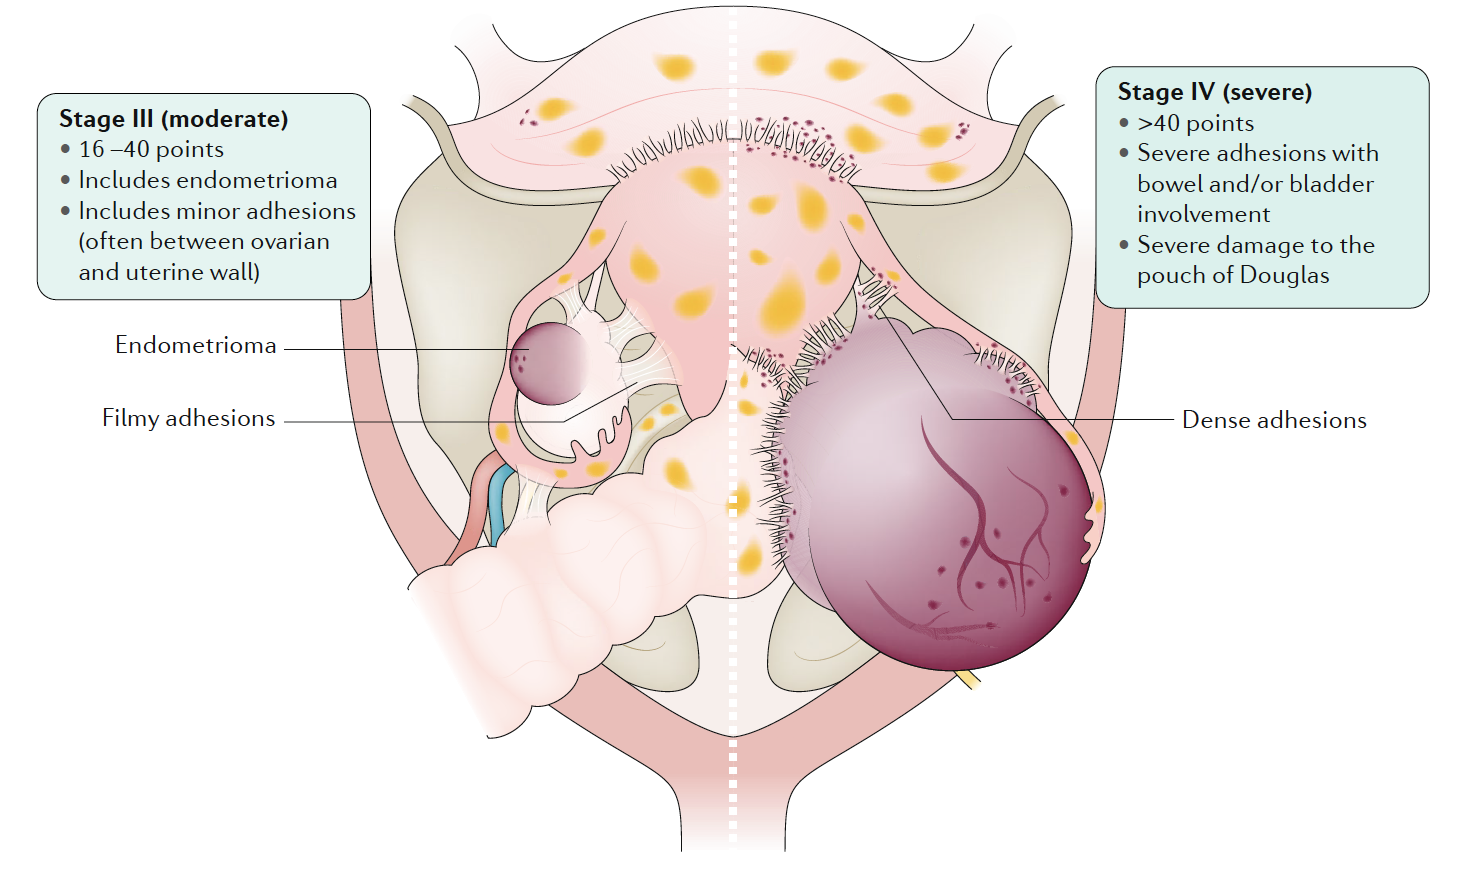

Endometriosis is a condition where endometrial-like tissue (membrane that lines the uterus) forms outside of the uterus. It is mainly found within the pelvic peritoneum (tissue that lines the pelvis), in the ligaments supporting the womb and the ovaries, and also less commonly in the appendix, bowel, or bladder. On rare occasions, we can also find endometriosis in the abdominal wall, belly button, liver, diaphragm, and lungs. Endometriosis is staged between the mildest form (level 1) to the severest form (level 4).

Stage 3-4 Pelvic endometriosis. Endometriosis, Nature Reviews Disease Primer, 2018, Vol 4(1) pp.9